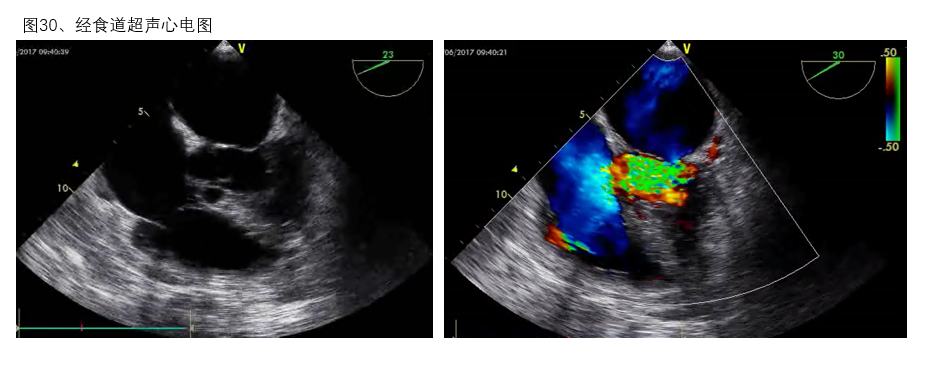

图29

2、经食道超声 与经体表超声相比,经食道超声实施的简便性相对较低,但是经食道超声可在胸腔内血管和心脏的探查中得到更加清晰的影像,是经体表超声的重要补充,也是双腔管留置时协助定位的重要辅助手段(图30)。

图30